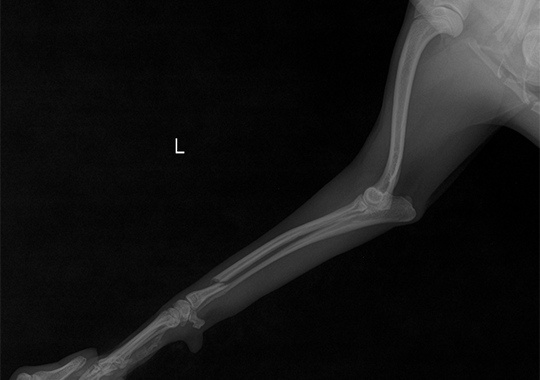

십자인대 파열 수술 전

십자인대 파열 수술 후

정형외과 케이스

본원은 실력 있는 전문 의료진과 최첨단 시설로 정형외과에서 좋은 예후들을 보여드리고 있습니다. 강아지에게서 쉽게 발생하는 슬개골 탈구, 십자인대 단열 뿐 아니라 다양한 고난도 케이스를 다루고 있으며, 특히 골절 수술은 회복률이 높고 타원 수술 후, 유합부전으로 본원에 내원하여 재수술에 성공한 사례가 많습니다.